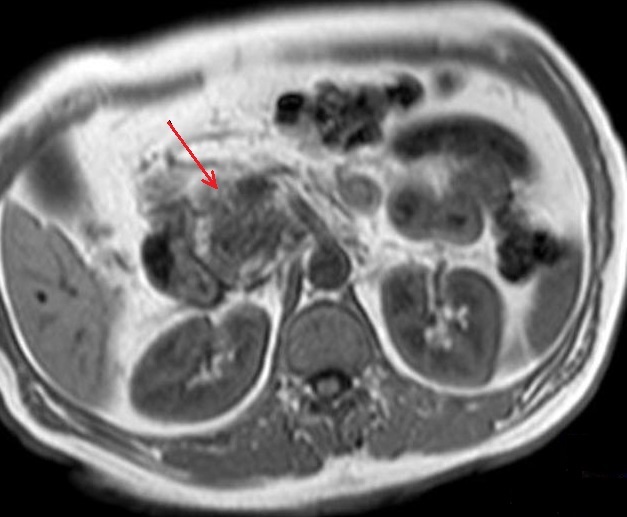

Image

radiologique IRM pondere sur T1 d'une adenocarcinoma

de la tete du pancreas . Aspect lesionnel tumorale

est hyposignal a bord flou , globulaire (

fleche rouge ) situe au tete du oancreas |

|

Mema cas en coupe

coronal . Le tumeur est hyposignal situe au

tete du pancreas ( fleche rouge ) |

Sur T2 le tumeur est hyposignal

avec sa contenue

peut en vue etre hererogene a discrete hyperintense

(fleche rouge ) . Coupe IRM axiale pondere

sur T2 , |

Meme cas en coupe coronale (

fleche rouge ) . Le tumeur est hyposignal et sa

contenue etre heterogene a discret hyperintense |